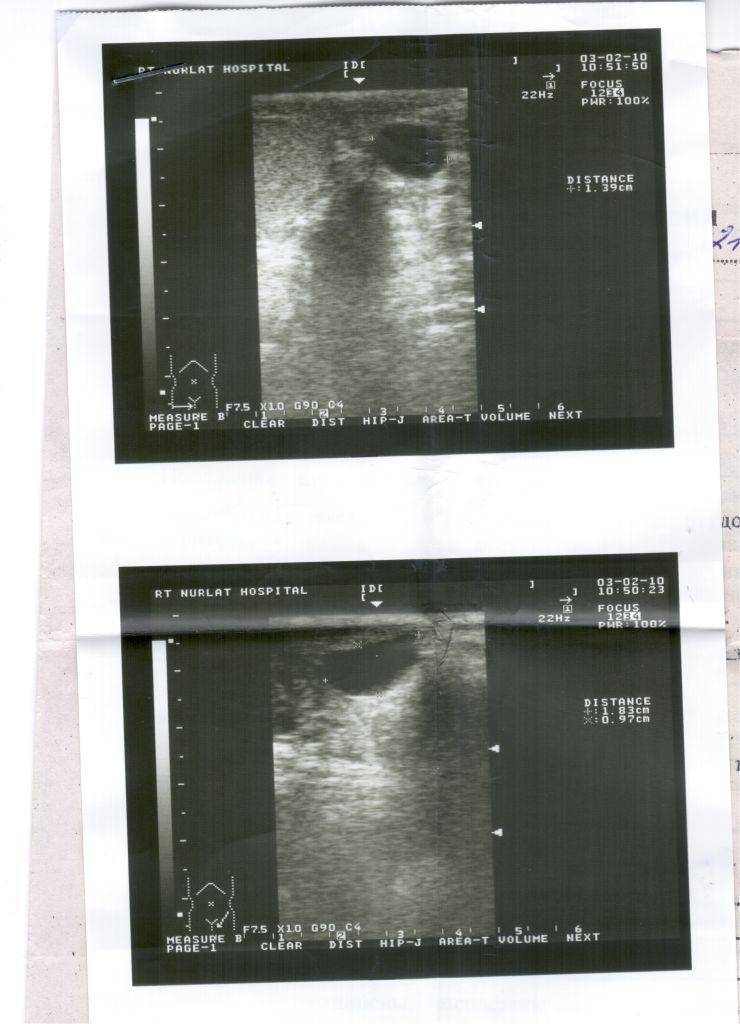

Посмотрите пожалуйста анализы УЗИ

Похоже, что у Вас - осумкованная гематома мошонки, возможно - в области придатка. Сделайте спермограмму, чтобы узнать Вашу фертильность( способность к оплодотворению). Обратитесь к урологу.